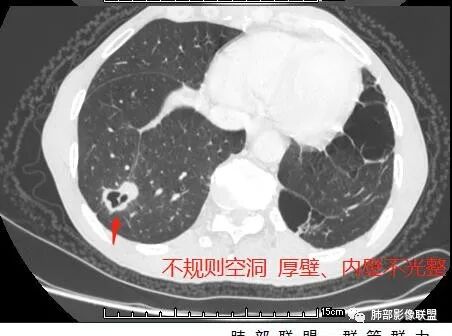

国内文献将空洞的形态、壁的厚度及内壁情况将转移性空洞大致分为4大类:

(1)囊样空洞, 呈圆形或类圆形, 直径>15 mm,壁薄 (1 ~ 2 mm)而均匀 ,内壁欠光整 ;

(2)小环形空洞 ,呈圆形 ,壁薄 (2 ~ 4 mm)而均匀 ,直径≤15 mm, 内壁光整;

(3)泡样空洞, 呈圆形或类圆形 ,壁厚 ( >4 mm),内壁光整;

(4)不规则空洞, 洞腔形态不规则, 壁厚 ( >4 mm)且不均匀, 内壁不光整;

其中囊样空洞和小环形空洞属于薄壁空洞,泡样空洞和不规则空洞属于厚壁空洞,其中腺癌空洞型肺转移瘤主要表现为小环形空洞,以下3个病例均表现为小环形空洞的转移瘤: